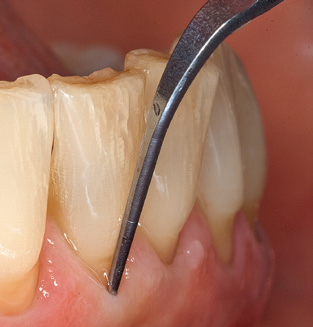

Fig. 4: Flexible probes with millimetre markings are recommended for the probing of dental implants (e.g. Colorvue Kit PCV11KIT6, Hu­Friedy). – Fig. 5a and b: A straight working tip (1P, W&H Dentalwerk Bürmoos GmbH) is a suitable instrument for use on all natural teeth. – Fig. 6: Curved working tips (3Pr/3Pl, W&H Dentalwerk Bürmoos GmbH) lend themselves to the processing of difficult-to-reach areas of the tooth and root surfaces (e.g. furcations). – Fig. 7: The tapered, hexagonal implant cleaning tip (1I, W&H Dentalwerk Bürmoos GmbH) permits atraumatic and efficient cleaning of the crown and abutment surfaces. – Fig. 8: Titanium and carbon curettes are suitable instruments for the manual cleaning of the implant surfaces.

Good illumination of the working field facilitates the process considerably. The system used by the authors achieves this thanks to a 5x LED ring integrated in the handpiece. Naturally, a range of working tips for different indications is also offered. A straight, universally employable tip is the basic instrument required for machine cleaning of natural teeth (Fig. 5a and b). Curved tips, which allow access to exposed furcations, are also available for hard-to-reach areas in the posterior region (Fig. 6).